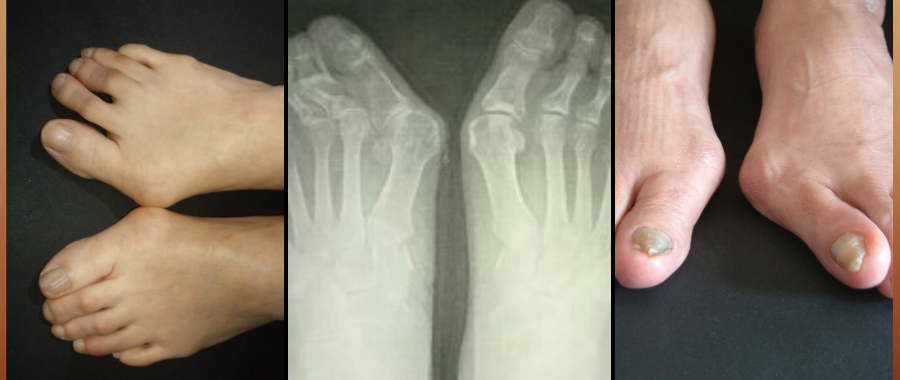

外反母趾の害は

外反母趾だけに止まりません。

靴の危険、リスクを正しく知らなければ

正しい靴選びへ進めません。